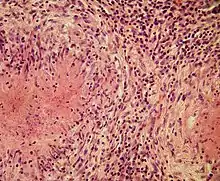

Structurally, epithelioid cells (when examined by light microscopy after stained with hematoxylin and eosin), are elongated, with finely granular, pale eosinophilic (pink) cytoplasm, and central, ovoid nuclei (oval or elongate), which are less dense than that of a lymphocyte.[4] They have indistinct shape and often appear to merge into one another, forming aggregates known as giant cells. When examined by transmission electron microscopy in epithelioid cells in the field of Golgi lamellar complex are taped not only zonated, but also sleek vesicles with dense center, and also great many (more than 100) large granulas with diameters up to 340 nm and with finegranular matrix more light than in macrophage granulas, sometimes with perigranular halo. “The most prominent feature of these cells is the enormous Golgi area; up to 6 individual stacks of Golgi cisternae may be present as well as a few bristle-coated and numerous smooth vesicles”.[5][4] Epithelioid cells have tightly interdigitated cell membranes in zipper-like arrays that link adjacent cells.[3] This cells are central in the formation of granulomas, which are associated with many serious diseases.[4] In granulomas, epithelioid cells perform the functions of delimiting.[3]

Epithelioid cells are an essential characteristic of epithelioid cell granulomas.[10] Epithelioid cell granuloma can be defined as specifically and structurally organized collection of epithelioid cells, macrophages, lymphocytes and dendritic cells. Foreign-body granulomas may be considered an organized collection of macrophages, including mere collections of giant cells surrounding inert substances like suture material – the so-called "non-immune granulomas." Granuloma formation is associated with pathogens that have learned to evade the host immune system by various means like resisting phagocytosis and killing within the macrophages. Indigestibility of matter by macrophages is a common feature of granulomatous inflammation.[4] Granulomas try to wall off these organisms and prevent their further growth and spread. Historically widespread and destructive diseases such as tuberculosis, leprosy and syphilis are granulomatous conditions. Granuloma formation is also the feature of many more contemporary conditions, like fungal infections, sarcoidosis and Crohn's disease.[4]